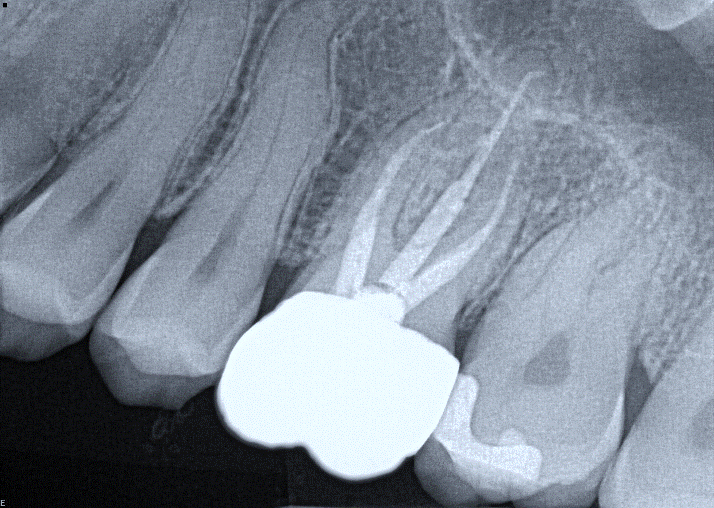

4. (Select ONE OR MORE correct answers)

What observation(s) can be made for tooth 3.6?